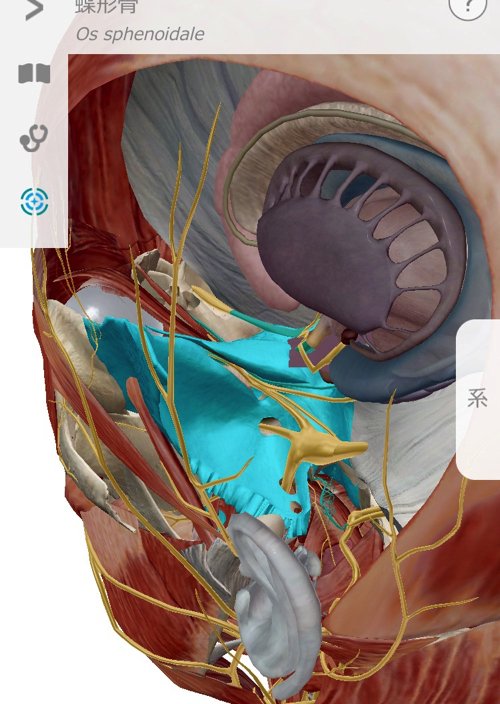

目の疲れは単純に目の周りの筋肉だけの問題ではありません。

コメカミ付近の頭蓋骨内部や神経類が複雑に絡み合う蝶形骨にも

目の疲れが影響を与えます。

最後に視神経のルートを辿りながら筋肉や頭骨の微調整をして終了です。